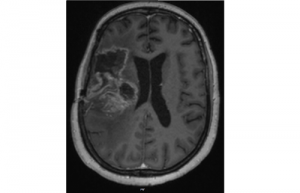

Mehr erfahren zu: "Neues Kontrastmittel erleichtert Frühdiagnose von Gehirnmetastasen" Neues Kontrastmittel erleichtert Frühdiagnose von Gehirnmetastasen Forscher des Leibniz-Forschungsinstituts für Molekulare Pharmakologie (FMP) haben einen Weg gefunden, Metastasen bestimmter Krebsarten im Gehirn mit möglichst wenig Kontrastmittel aufzufinden. Das Team nutzt dafür ein synthetisches Molekül, mit dessen […]